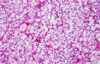

Renal Cell Carcinoma

Clear Cell RCC

Clear Cell RCC

Papillary RCC

Papillary RCC

Chromophobe RCC